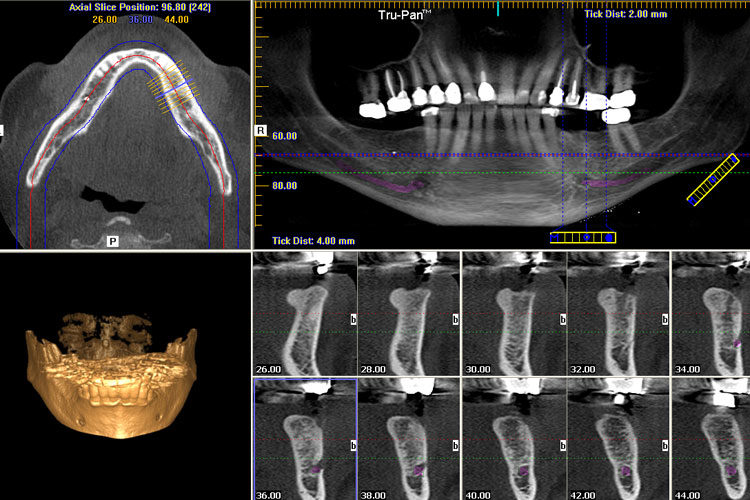

1. Cone Beam Computed Tomography (CBCT) in Modern Workflows: Architectural Integration

CBCT has evolved from a standalone diagnostic tool to the structural backbone of precision-driven digital workflows. Its integration is no longer optional but foundational for implantology, endodontics, and complex prosthodontics.